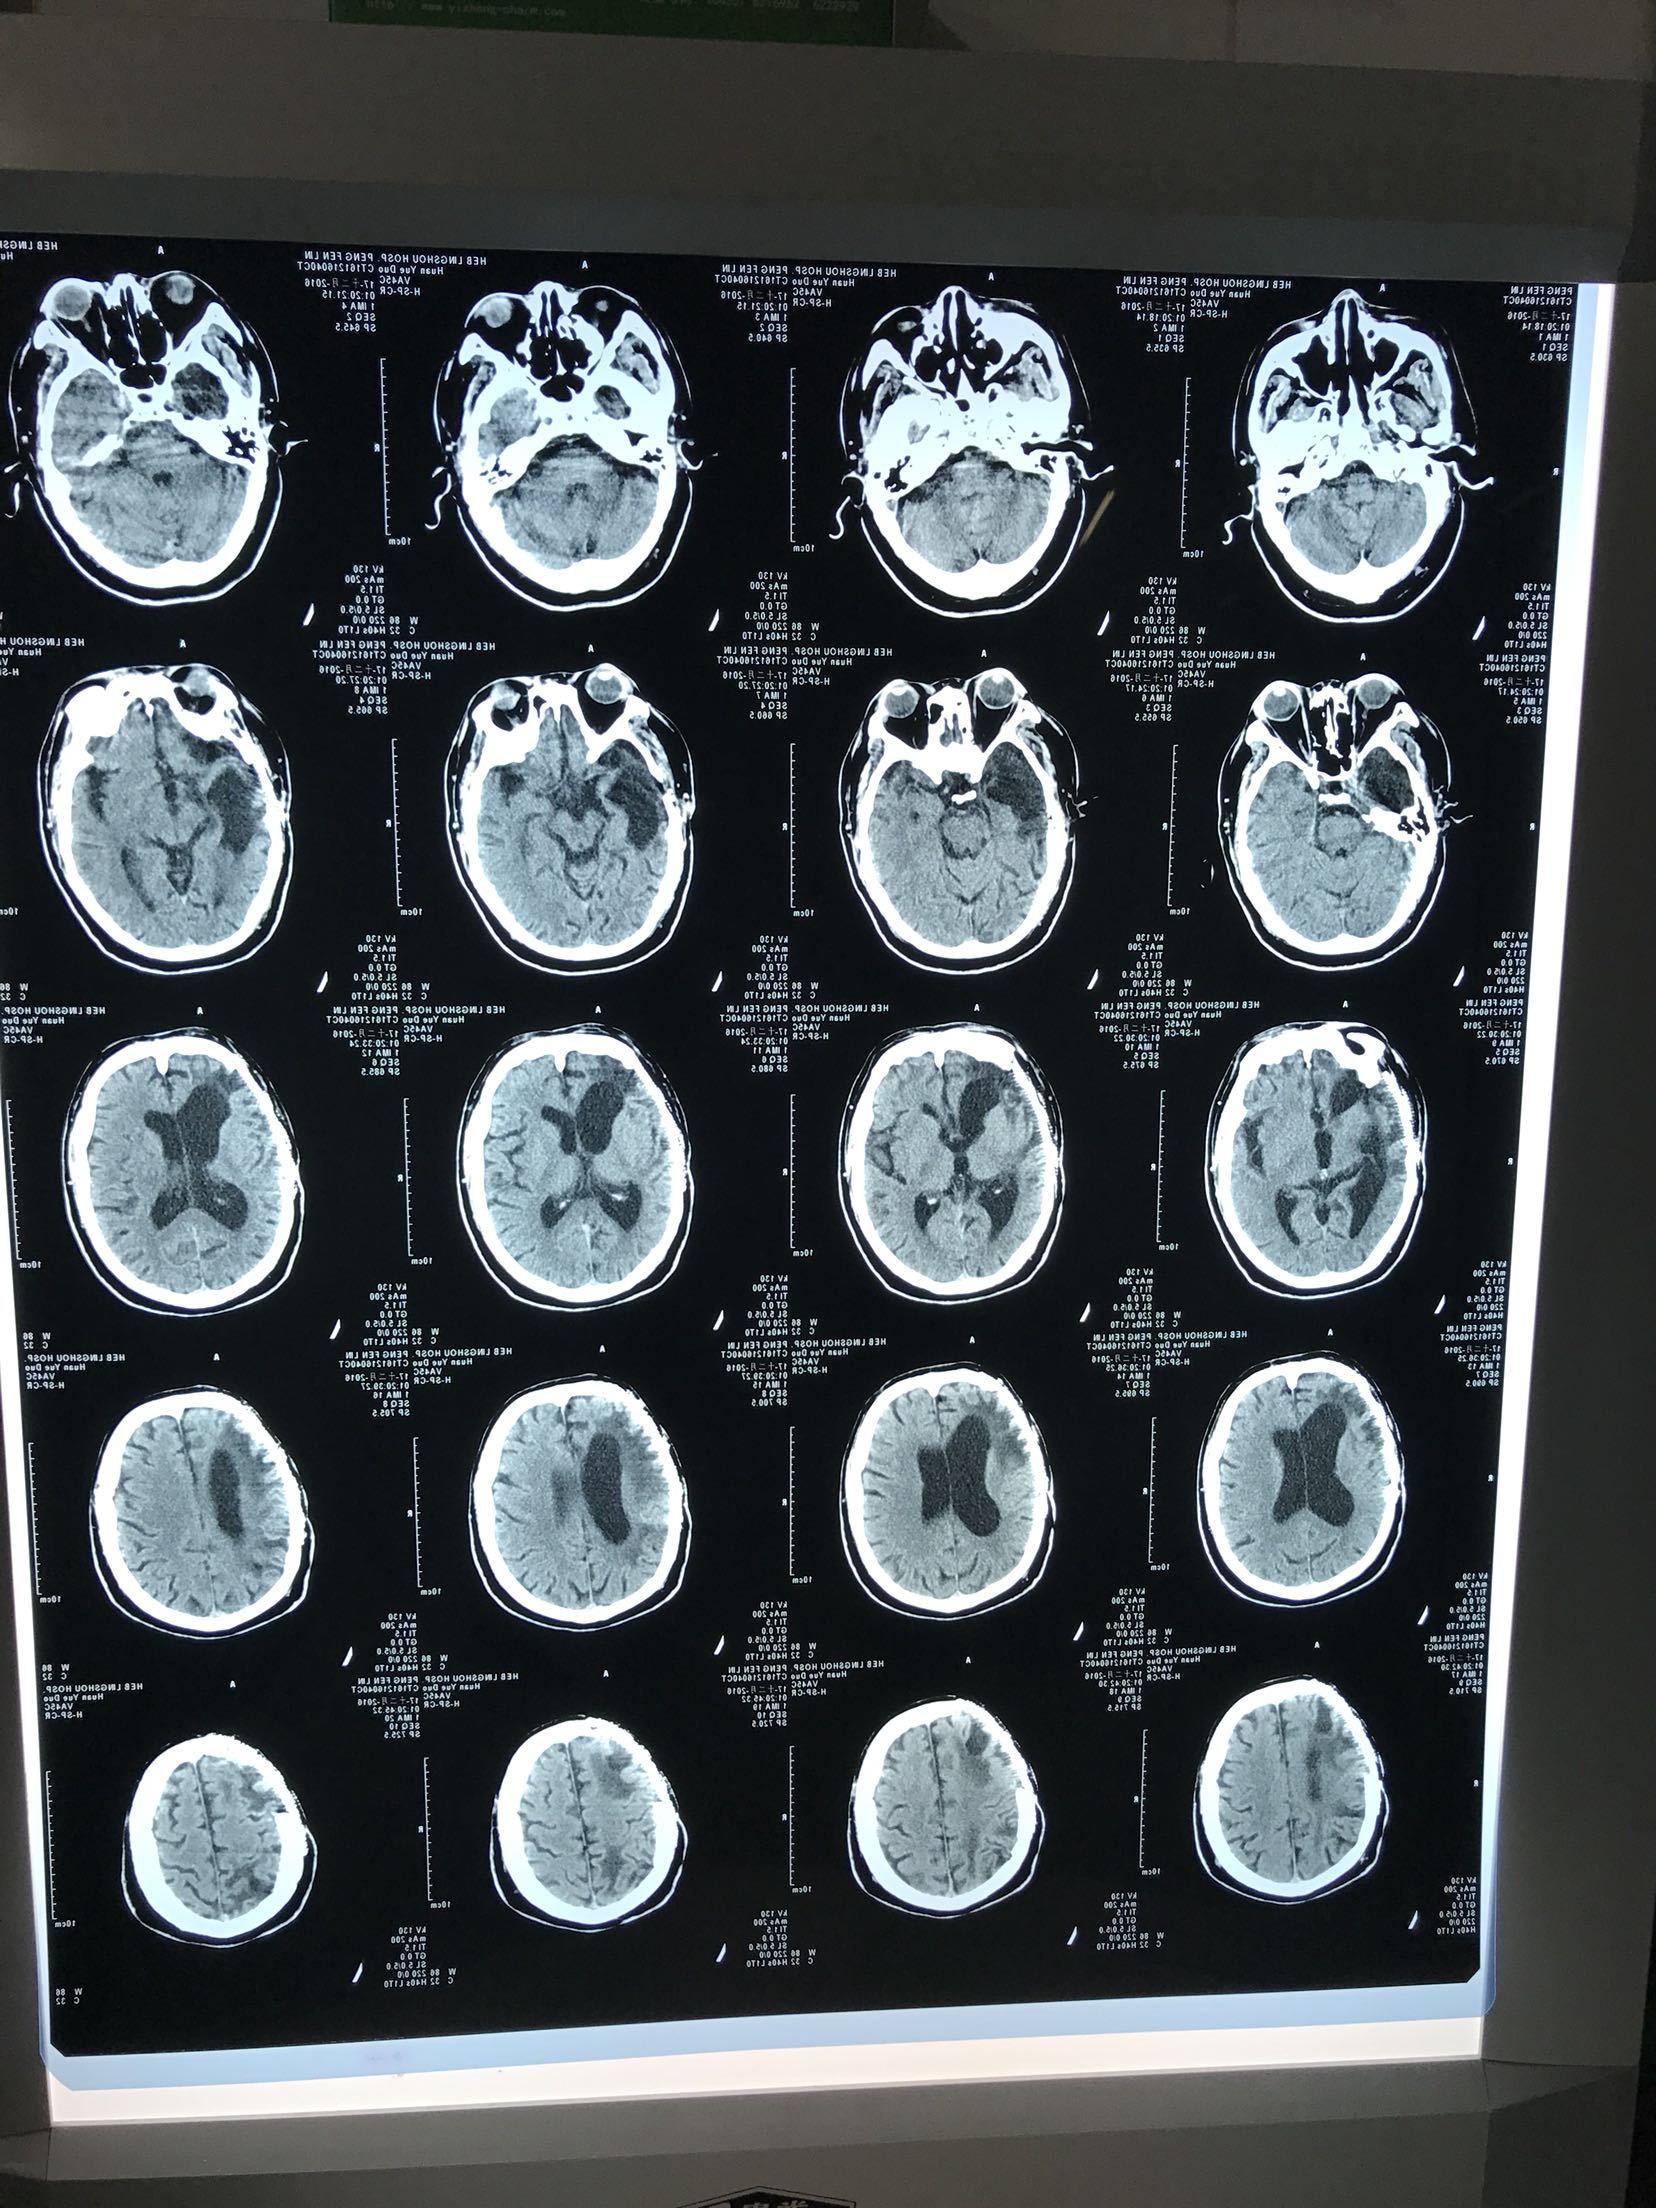

抽搐后意识不清约1.5小时,患者中年男性,既往脑外伤病史,术后遗留癫痫发作,平素口服奥卡西平,未有其他病史。患者源于入院前1.5小时,睡眠中突发抽搐,伴小便失禁,间断抽搐两次,每次持续10分钟,急打120接入我院。急诊查头Ct:1.右侧额颞顶颅骨成型术后改变,2.右侧额颞顶部软化灶伴右侧脑室扩张,为进一步治疗收住我科

T36.0℃,呼吸15次/分,脉搏102次/分,血压126/80mmhg,意识模糊,双瞳孔约5毫米,对光反射迟钝,双肺呼吸音粗,心音有力,腹无压痛,肠鸣音可,双巴氏征阴性,

颅脑外伤术后 癫痫持续状态,给于镇静抗癫痫等治疗